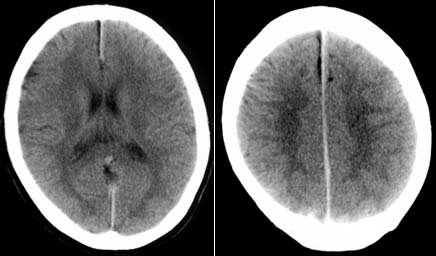

脳浮腫は、医師にとって適切な検査なしに診断するのが難しい状態です。診断は症状と根本的な原因によって異なります。

医師が脳の腫れを診断するために使用する一般的な手順には、次のようなものがあります。